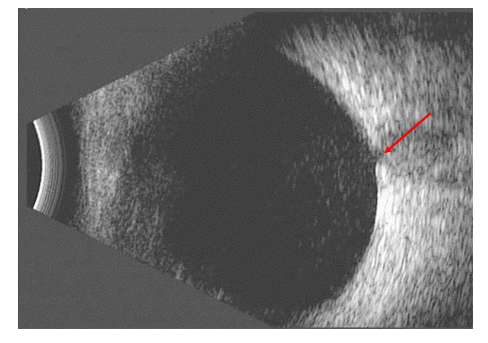

图3 B超图像

Figure 3 B-scan image

玻璃体混浊、视乳头小凹陷(箭头)。

The mild vitreous opacities and small excavation of the optic never head (arrows).